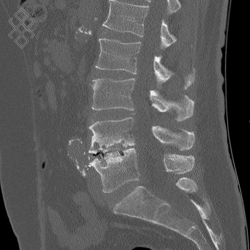

Scanner du Rachis lombaire